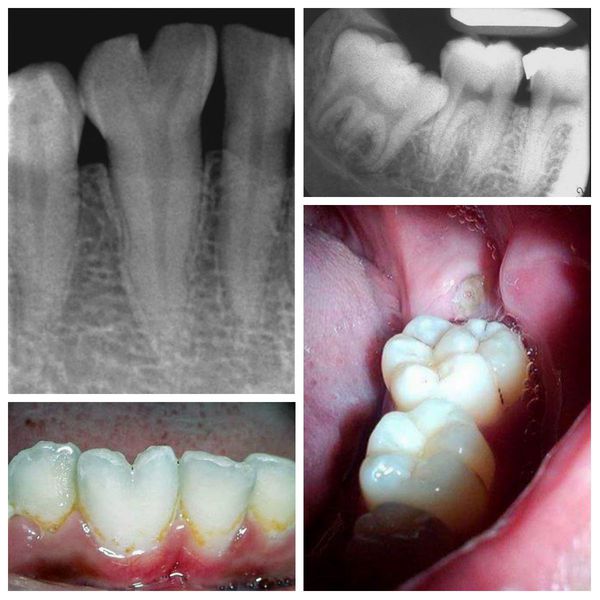

Podwojenie i zlanie zębów (fuzja lub germinacja) najczęściej prowadzą do problemów estetycznych — zęby wydają się zbyt duże, asymetryczne lub mają nieregularny kształt. Od typowego stłoczenia zębów (stłoczenie zębowe) można je odróżnić jedynie na podstawie badania rentgenowskiego, które pokazuje, czy zęby mają wspólne korzenie lub komory miazgi.

Zaburzenia takie jak zrośnięcie (fuzja) czy podwojenie zębów (geminacja) najczęściej dotyczą zębów przednich, szczególnie siekaczy, natomiast zrost korzeni (ankyloza, zrośnięcie) spotyka się głównie w obrębie drugich i trzecich trzonowców (molares) szczęki.

Do postawienia rozpoznania wystarczające jest badanie kliniczne uzupełnione zdjęciem rentgenowskim (radiogramem), które pozwala na ocenę liczby i kształtu korzeni oraz stopnia ewentualnego zlania tkanek.

Rozdwojony ząb (po lewej) i zrośnięte zęby (po prawej): wygląd zewnętrzny i zdjęcie rentgenowskie

2. Fuzja i zrośnięcie zębów (fuzja, zrastanie zębów)

Podejrzenie fuzji pojawia się, gdy podczas leczenia ortodontycznego ząb nie reaguje na siły przesuwające lub podczas ekstrakcji stawia nietypowy opór. W takich przypadkach wykonuje się zdjęcie rentgenowskie (radiogram), które potwierdza zrost korzeni.

Leczenie obejmuje:

• dewitalizację (leczenie kanałowe, usunięcie miazgi) – gdy połączenie obejmuje tkanki zęba;

• chirurgiczne rozdzielenie korzeni (separacja korzeni) – jeśli to możliwe technicznie i funkcjonalnie.

Po zabiegu powierzchnie zębów zabezpiecza się materiałem kompozytowym lub koroną, aby przywrócić estetykę i funkcję.